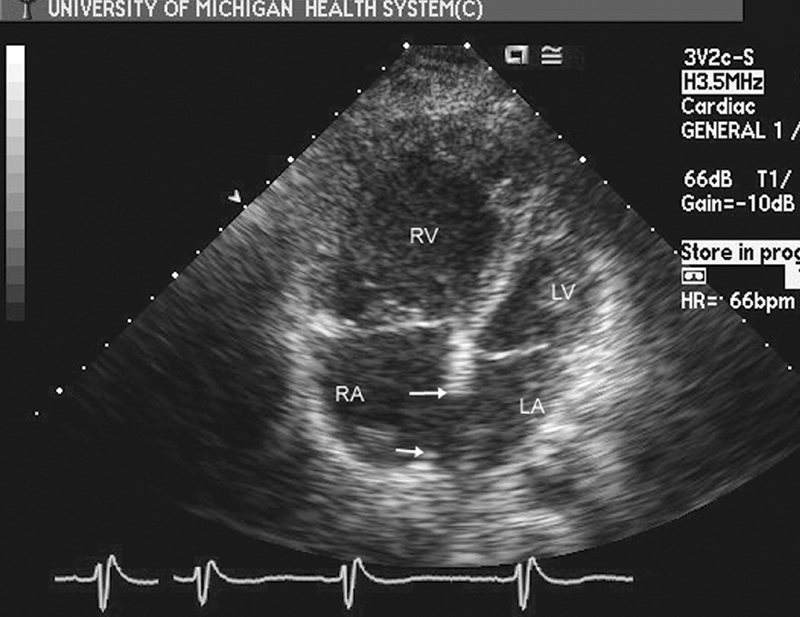

فحوصات تشخيصية لبعض امراض القلب والشرايين التاجية